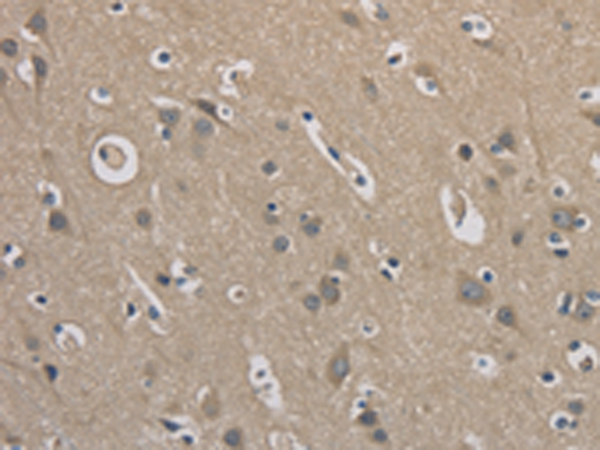

分类: 科研抗体货号: P07216别名: NOC4, COX4NB, C16orf2, C16orf4, FAM158B应用: WB,IHC反应种属: Human, Mouse, Rat